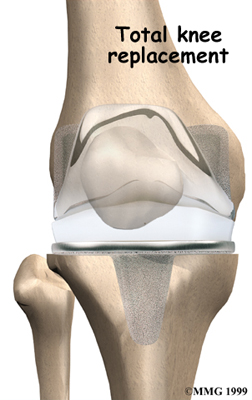

Artificial Knee Replacement

An artificial knee replacement is the ultimate solution for advanced knee OA.

Surgeons prefer not to put a new knee joint in patients younger than 60. This is because younger patients are generally more active and might put too much stress on the joint, causing it to loosen or even crack. A revision surgery to replace a damaged prosthesis is harder to do, has more possible complications, and is usually less successful than a first-time joint replacement surgery.

Related Document: FYZICAL Oak Park Lake Charles Guide to Artificial Joint Replacement of the Knee